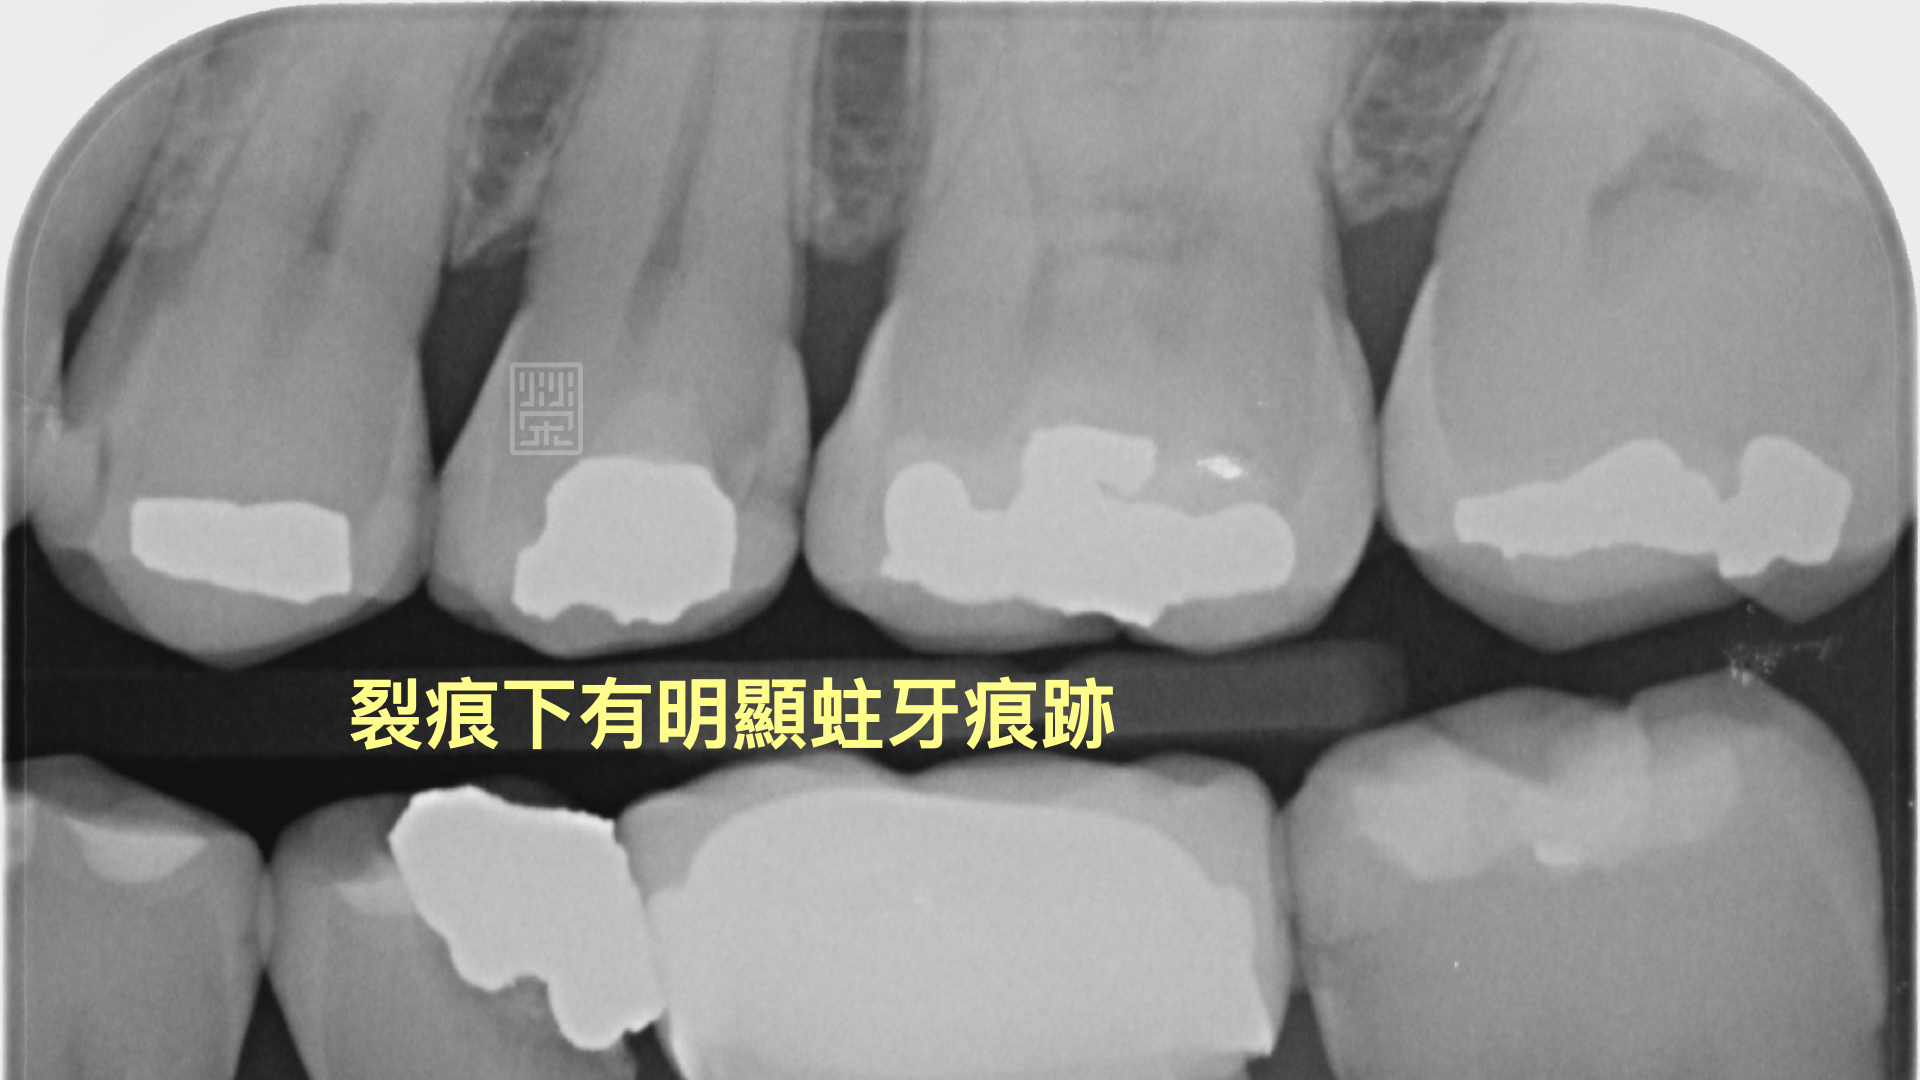

裂痕相對位置下的X光片,可以明顯發現蛀牙